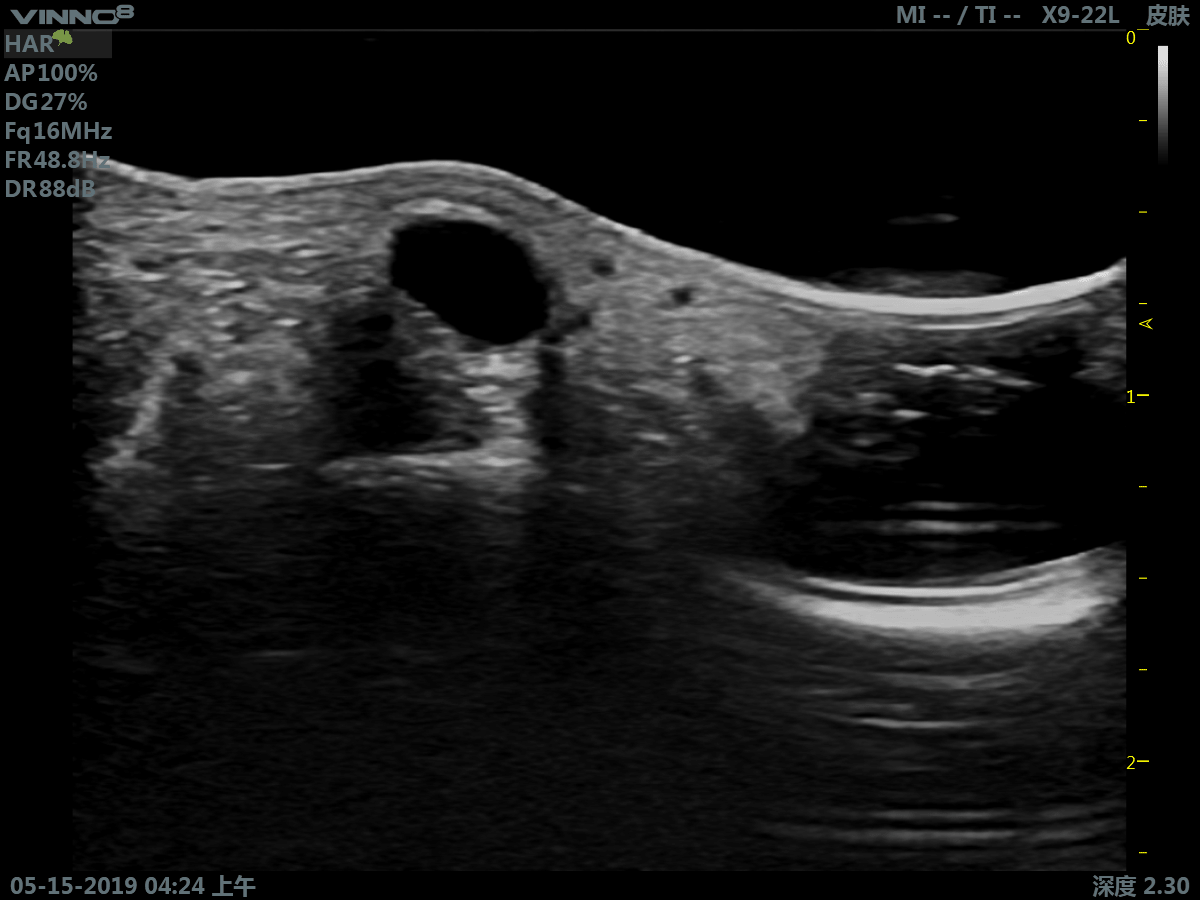

Портативный ультразвуковой сканер VINNO 8

Преимущества портативного УЗИ аппарата VINNO 8

- инновационная платформа RF обеспечивает суперчистое изображение в результате сверхвысокой скорости обработки данных

- сверхвысокая частота (до 23 МГц на линейном датчике)

Клиническое применение:

- мелкие объекты (включая щитовидную железу, молочную железу, семенники и т.д.)